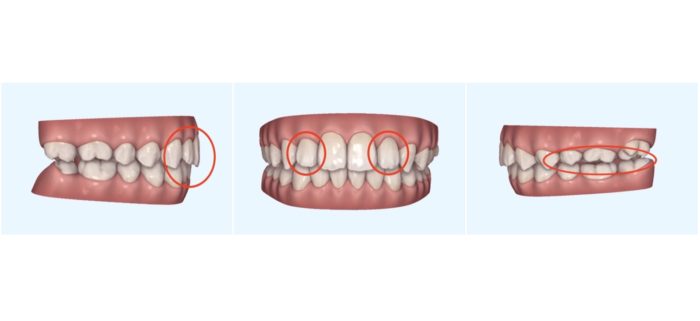

こちらは、1回目のアライナー(マウスピース)をすべて使用し終えた時点のお口の中の状態です。

全体的に歯がきれいに並んできましたが、上の2番目の歯(側切歯)に左右ともわずかなねじれが残っていました。(画像中央)

また、奥歯のかみ合わせがまだ十分にかみ合っていない状態も見られます。(画像右)

横から見ると、上の前歯の前方への傾き(出っ歯)もわずかに残存していました。(画像左)

そのため、より理想的な歯並びと咬み合わせを目指し、追加アライナーで細かな調整を行うことにしました。

追加アライナーは全部で25枚。

1回目と同様に1週間ごとに交換し、約6カ月かけて進めていただきました。